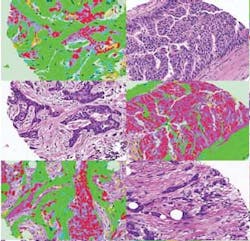

To automate the process, researchers at the Stanford University (Stanford, CA, USA; www.stanford.edu) schools of engineering and medicine have developed a software-based system called Computational Pathologist, or C-Path, that can objectively and accurately assess images of breast cancer tissues to predict patient survival.

The researchers use existing tissue samples taken from patients whose prognosis is known to train C-Path. The computers measure various structures of the tumors and attempt to use them to predict patient survival. By comparing results against the known data, the mathematical models are then automatically adapted to better predict survival and discover what features of the cancers matter most and which matter less in predicting survival.

Once trained using one group of patients, C-Path evaluated tissues of cancer patients not checked before and the result was compared against known data. Ultimately, C-Path yielded results that were a statistically significant improvement over human-based evaluation.